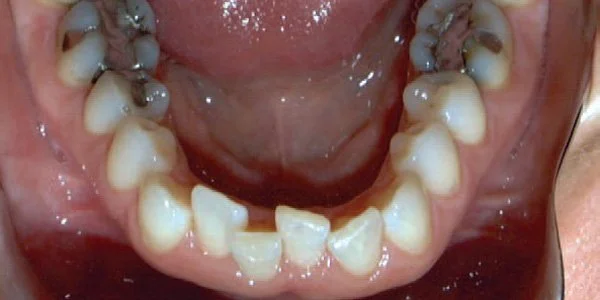

Crowding

Teeth are out of alignment due to lack of space